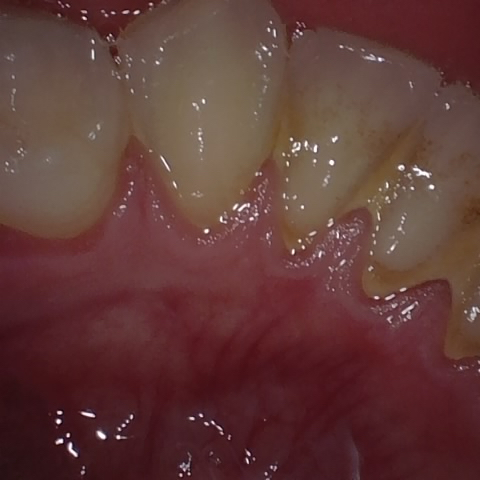

Annotated as "Good"